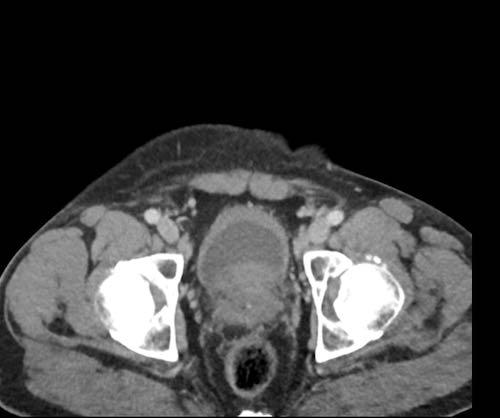

Ở vùng chậu, vị trí quan trọng nhất là túi cùng trực tràng-tử cung và trực tràng-bàng quang (túi cùng Douglas).

Đôi khi có thể thấy di căn khối u lan ra phía trước bàng quang, nhưng không xâm lấn thành bàng quang, do bàng quang là cơ quan nằm ngoài phúc mạc.

Tuy nhiên, vòm bàng quang phía trên và ống niệu rốn được ngăn cách với khoang bụng bởi một lớp phúc mạc thành, tạo thành đích tiềm năng cho các tế bào khối u.

Đặc biệt khi bàng quang đầy, các tổn thương di căn phúc mạc có thể được quan sát thấy ở phía trước bàng quang, áp sát thành bụng trước.

Đây không phải là bệnh lý quanh bàng quang, vì khoang quanh bàng quang nằm ngoài phúc mạc và không thông với khoang trong phúc mạc.